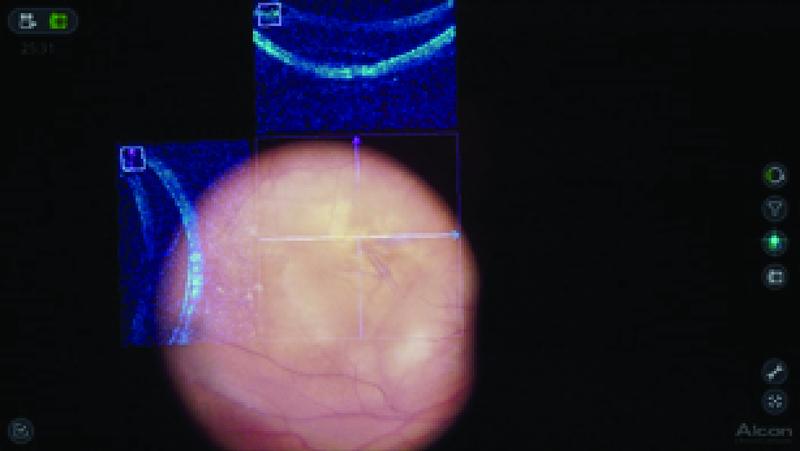

Figure 2.

Intraoperative snapshot showing fs-ILM peeling using 3-D surgical viewing and I-OCT. The I-OCT shows no evidence of any iatrogenic complication.

The anesthetists performed sedation and a retrobulbar block. The NGENUITYⓇ digitally assisted vitreoretinal surgery system (Alcon, Inc., Fort Worth, TX) was connected to replace the oculars of the microscope. The 3-D high definition real-time video was displayed on the NGENUITYⓇ4K 3-D flat-panel placed at 1.3 m from the surgeon. To be able to see in 3-D, the surgeon wore polarized glasses. Traditional vitreoretinal techniques, with the Constellation Vision System (Alcon, Inc, Fort Worth, TX), were performed without obstacles, including core vitrectomy, posterior hyaloid detachment, and peripheral vitrectomy. Brilliant blue G (DORC, Zuidland, the Netherlands) was used to stain the ILM and the surgeon performed fs-ILM peeling using disposable 25-gauge end-grasping forceps under I-OCT [Figure 2]. The I-OCT also proved that there were no iatrogenic lesions [Video 1], so it was decided not to perform gas tamponade. The subfoveal macular thickness improved from 706 µm (preoperative), 540 µm (after one month), 214 µm (after four months) to 221 µm (after seven months) [Figure 3] and the visual acuity improved to 20/40 after seven months of follow-up.